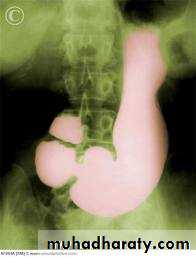

Hypertrophic pyloric stenosisCause:A. Congenital typeB. Adult type

Epidemiology

Pyloric stenosis is relatively common and has a male predilection (M:F ~ 4:1), and is more commonly seen in Caucasians 4. It typically occurs between the 4-8 weeks of life. There may be a positive family history. Incidence of hypertrophic pyloric stenosis is approximately 2-5 per 1,000 births per year in most white populations,Hypertrophic pyloric stenosis refers to idiopathic thickening of gastric pyloric musculature which then results in progressive gastric outlet obstruction

In a normal situation, the pyloric muscle thickness (diameter of a single muscular wall on a transverse image) should normally be less than 3 mm (most accurate 3) and the length (longitudinal measurement) should not exceed 15 mm.